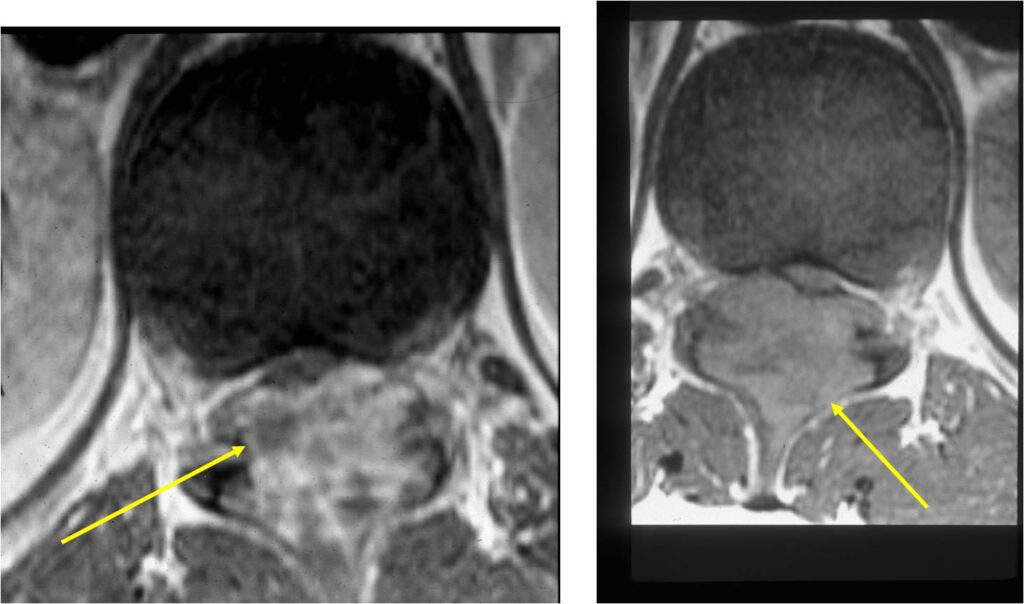

MRI:

- Also useful in determining extent

- There is often extensive edema around the tumor in the surrounding bone and soft tissues that can lead to a misdiagnosis of a malignant tumor.

- Spine (40% of cases; usually posterior elements)